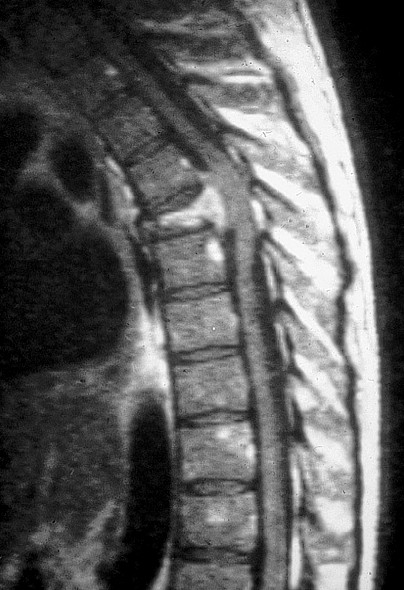

Fig. 1.7. Apport de l’IRM (séquence pondérée en T1) en cas de métastase vertébrale ou de myélome.

Hypersignal hétérogène (prise de contraste après injection de gadolinium) d’une vertèbre tassée qui comprime la moelle thoracique